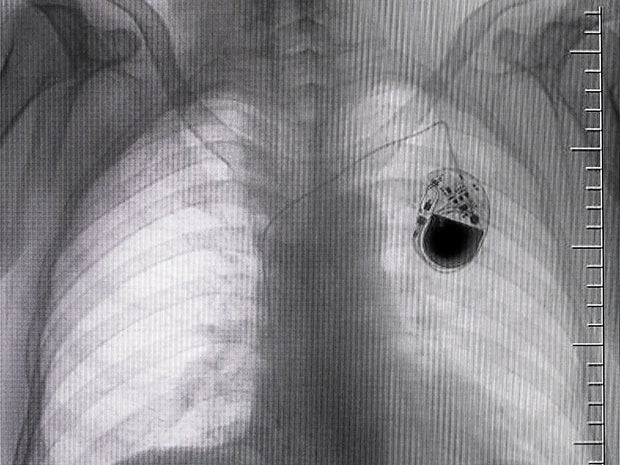

Radiology is the science of high-energy radiation for the diagnosis and treatment of disease. Teleradiology extends this definition into the transmission of radiological patient images — X-rays, CT scans and MRIs, for example.

- Projection (plain) radiography (X-ray): produced by transmitting X-rays through a patient. Film has been replaced by computed radiography (CR) and more recently by digital radiography (DR). Plain radiographs can be used to identify various types of arthritis and pneumonia, bone tumors (especially benign bone tumors), fractures and congenital skeletal anomalies.

- Computed tomography (CT scan): CT scans use X-rays combined with computing algorithms to create an image of the body. Often used for urgent or emergent conditions including cerebral hemorrhage, pulmonary embolism (clots in the arteries of the lungs), aortic dissection (tearing of the aortic wall) and obstructing kidney stones.

Teleradiology is the transmission of radiographic images from one location to another for sharing studies with other radiologists and physicians. The benefits of teleradiology mirror the benefits of telehealth. A doctor who needs the results of a scan can transmit that image to the West Coast or overseas to ensure a timely reading.

The primary benefit of blockchain technologies, when applied to teleradiology, is “truth,” not “trust” by offering an integrity check on patient images. Yesterday, radiologists had to trust that images were accurate and unaltered — but they had no proof. Today, they have truth — immutable evidence that the images they are reading are unchanged.

Immutable patient images

We can expand the business case of teleradiology to include image transmission. By using blockchain technology, improved patient image immutability ensures that a provider can validate that the image and diagnosis are unchanged. Providers can verify that they are reviewing the latest copy and confirm the “right” image version was received.